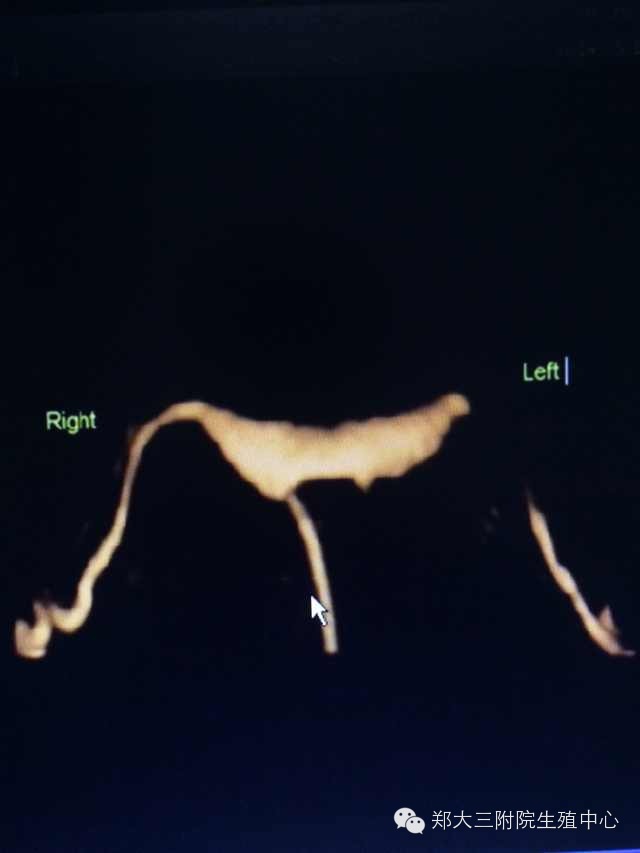

子宫输卵管超声造影(3D/4D-Hycosy)是在三维/四维阴彩下将造影剂经置入宫腔的导管注入子宫和输卵管,显示子宫腔和输卵管形态、位置、以发现宫腔和输卵管内病变、畸形以及评估输卵管通畅性的一种检查方法。

2、图像清晰、可三维立体成像、四维动态录像显示子宫、输卵管、盆腔造影的过程,更直观,便于临床医师观察;

3、对子宫输卵管畸形可明确诊断;

4、对输卵管异常显影如僵硬、扭曲、纤细、角状反折或盘曲的判断更精确;